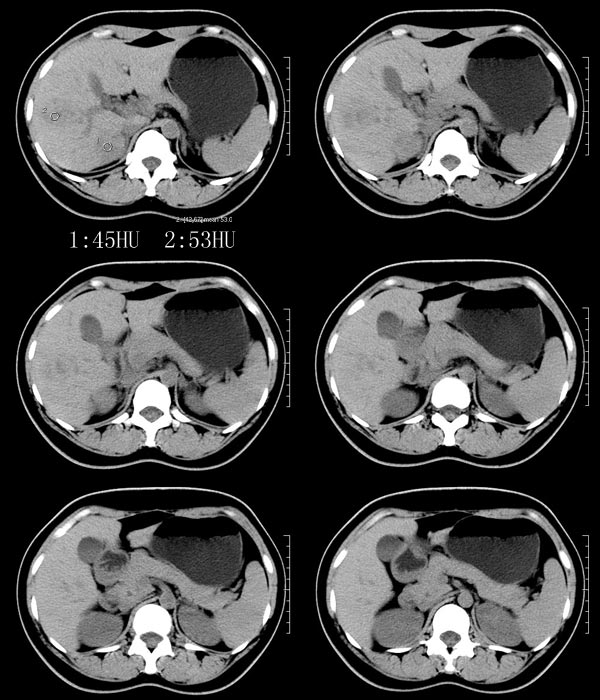

以下是引用52yingxiang在2007-9-16 10:16:00的发言:[br]肝脏局灶性结节增生影象表现(fnh)[br][br]肝脏局灶性结节增生是一种少见的肝脏良性肿瘤,可表现为边界清楚并无包膜的实质性肿块。病变大小不一,多系单发,亦可多发。组织学上是由结构紊乱的肝细胞、库普弗细胞、胆管、血管和粗厚的纤维性间隔所组成。[br]局灶性结节增生的ct表现可归纳为6点:[br]1、密度变化是其特征性改变,平扫多为低密度,少数为等密度,无论增强的早期或晚期均可能呈等密度,增强扫描有助于发现平扫为等密度的病灶;[br]2、中心疤痕,部分病灶在动态ct扫描时早期可看到中心疤痕增生性结节性病灶,ct血管造影也可看到普通ct不能显示的车轮状血管和车轴样改变;[br]3、纤维性分隔影,平扫为低密度,增强后为高密度;[br]4、包膜征象,增强后可以出现包膜强化,晚期较明显;[br]5、邻近血管的改变,主要是肝静脉受压,是发现等密度病变的重要依据;[br]6、瘤内胆管显影,这需要在胆管造影增强的情况下方能显示,出现率不高。[br][br]本例特点: 平扫低密度,增强动脉期明显强化,中心点条状低密度影(考虑纤维瘢痕),静脉期及延时期明显退减并与肝呈等密度,但中心仍可见低密度灶。[br]考虑肝脏局灶性结节增生(fnh)